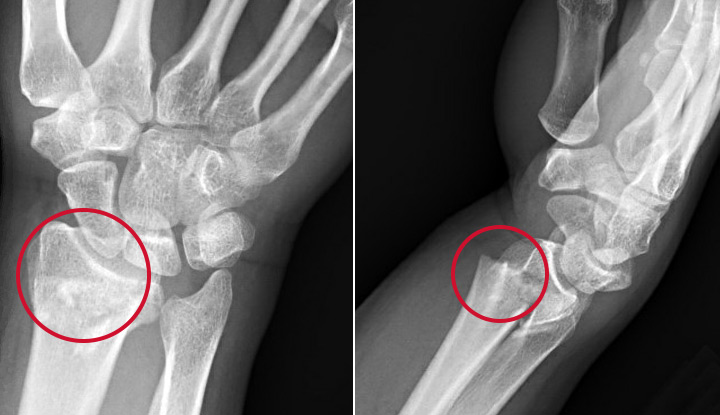

Dr. Italiya has extensive expertise in trauma care, joint replacement surgeries (knee & hip), fracture management, arthritis treatment, and spine-related conditions. His approach focuses on long-term recovery and functional restoration rather than temporary pain relief.

Specialized orthopedic trauma care for fractures, injuries, and medico-legal cases with immediate medical attention.